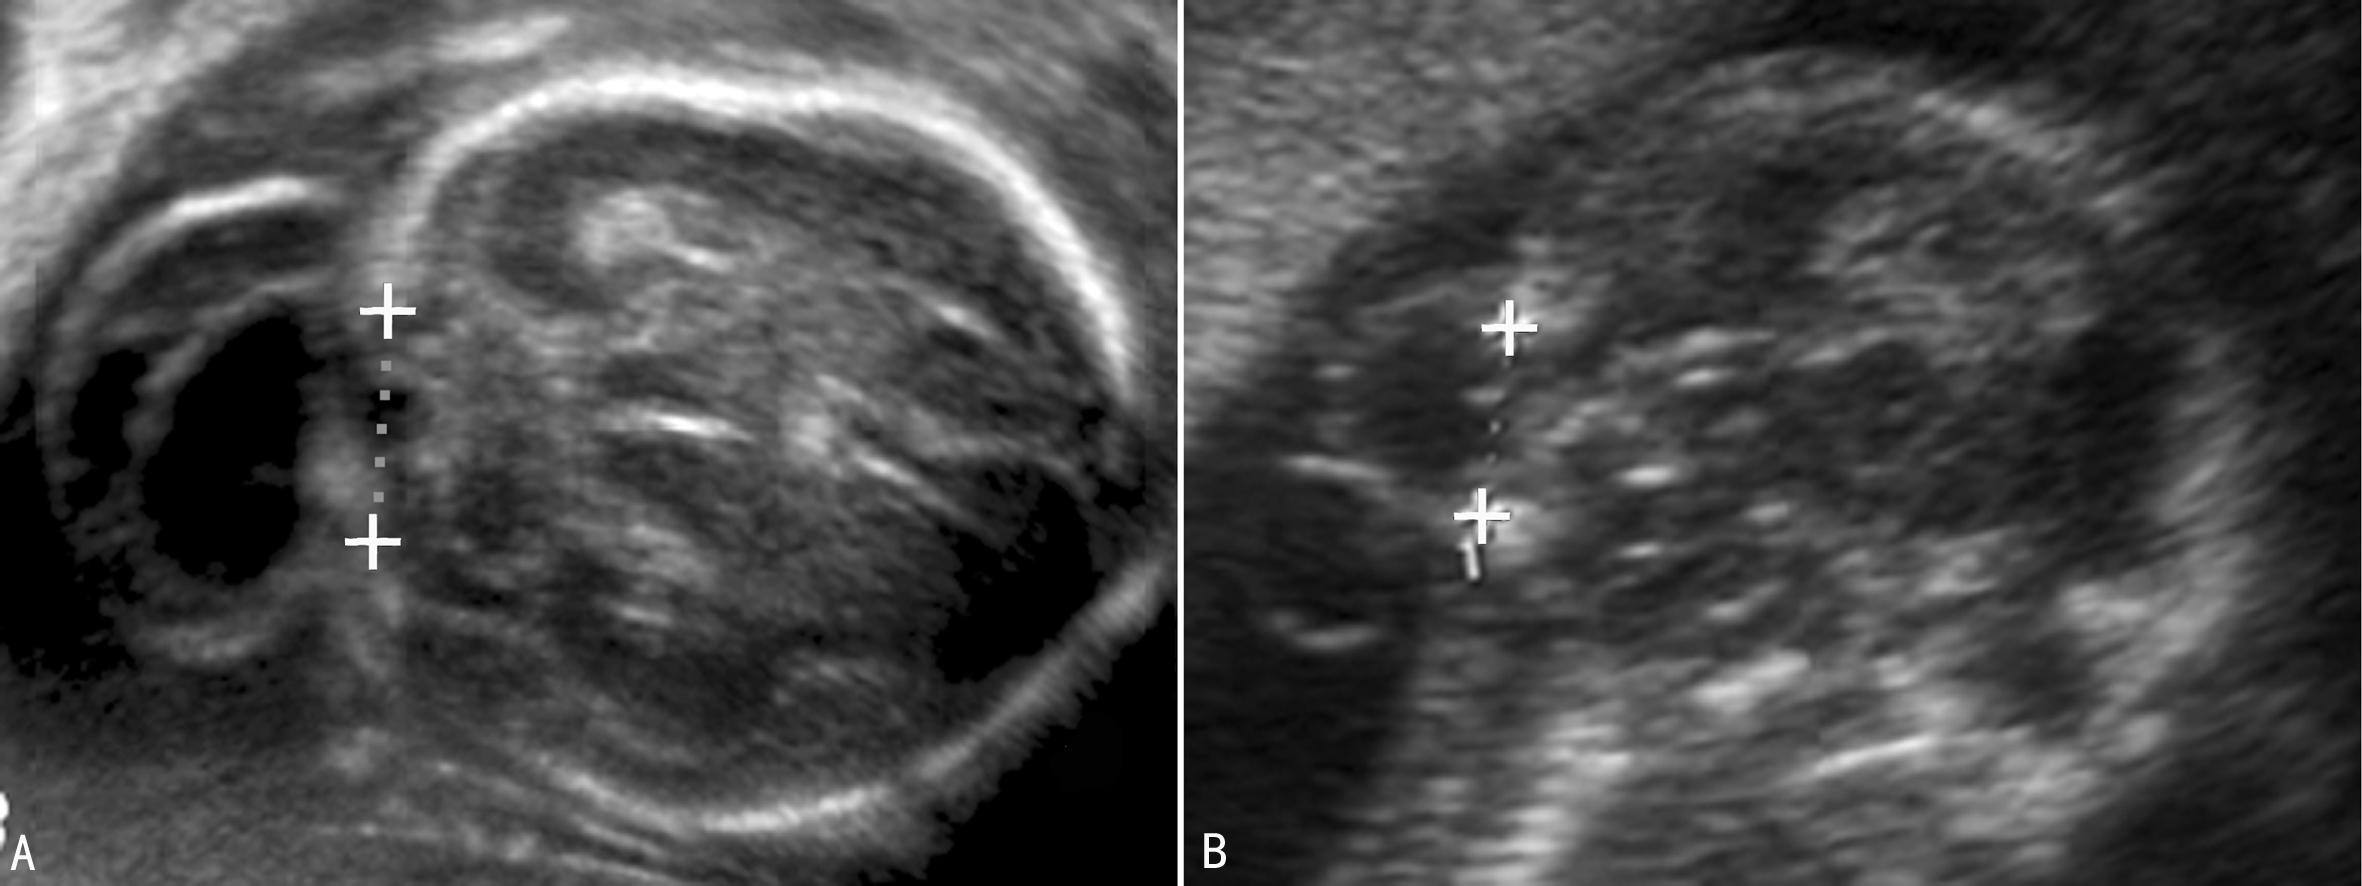

早孕期头颅小或者颅骨形态不规则,在头部轮廓外可显示包块样回声;随着胎儿的生长图像显示的愈加典型。经阴道超声可以看到早孕晚期的颅骨缺损处。胎儿颅骨显示后可以在颅骨外显示包块回声,局部颅骨显示缺损(图1),通过相互垂直的两个断面测量颅骨缺损的大小可以评估缺损的面积及突出物的大小(图2,图3)。有些小的缺损不能显示,仅能看到颅骨旁突出去的小囊样结构。突出的回声内部由于疝出的组织不同而有不同的表现,呈囊性或者囊实性混合回声(图1),“囊套囊”或者“靶环征”提示第四脑室脱垂,突出至颅底及眼部的脑膜膨出常难以于产前做出诊断。70%~80%伴有脑室扩张(图1A),25%伴小头畸形。除脑部异常回声外,其他部位检查可以发现伴发的畸形。

图1 14周胎儿脑-脑膜膨出声像图(箭头)

图2枕部缺损大小的测量(A:左右径 B:上下径)